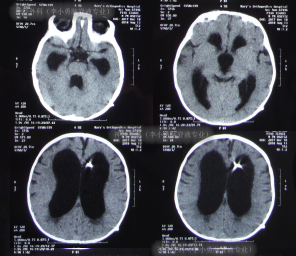

脑脊液各项化验均正常后,于2018年9月26日进行了脑室腹腔分流术,术后当天复查头颅CT示脑室分流术后状态(图-8)。

图-8:2018年9月26日头颅CT

分流术后第9天即2018年10月5日(李小勇脑脊液专业住院治疗2个月)出院,出院时:精神状态佳,“对眼”完全消失,呕吐消失饮食正常;出院时头颅CT示无异常(图-9)。

图-9:2018年10月5日出院时